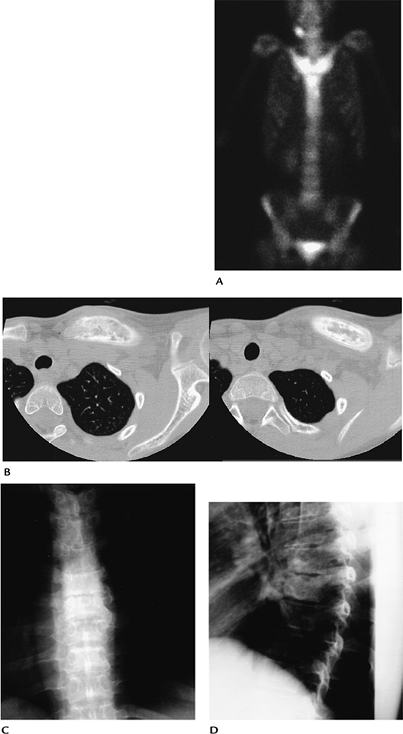

![]() |

FIGURE 11-4 SAPHO. (A) Radionuclide scan demonstrates intense uptake in the medial clavicles and sternum. (B) Axial CT image demonstrates thickening and sclerosis of the clavicle. AP (C) and lateral (D) radiographs of the spine demonstrate vertebral sclerosis and endplate irregularity caused by discitis.